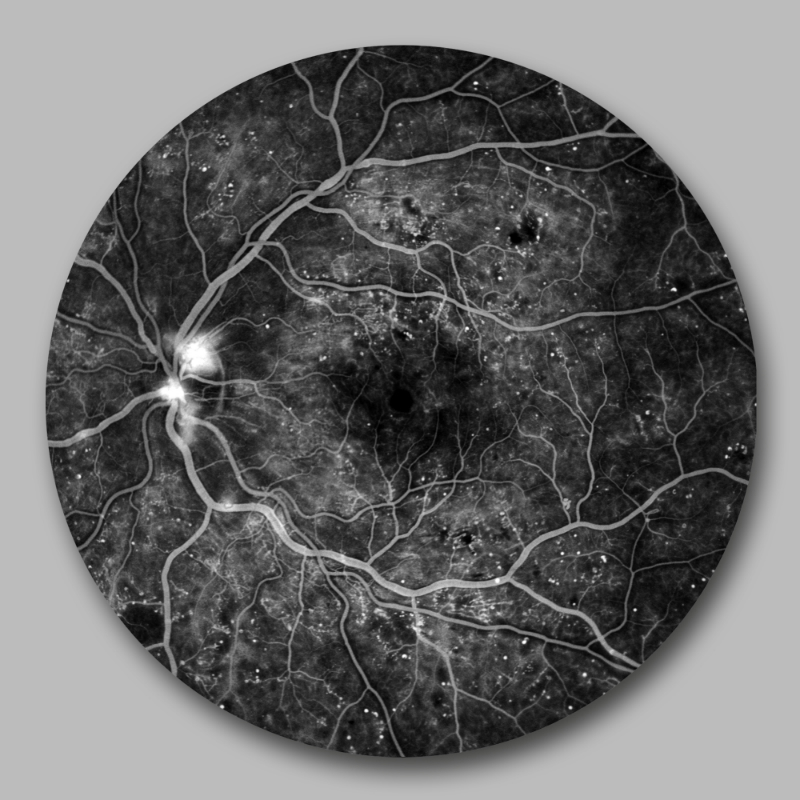

Die Netzhaut am Augenhintergrund ist die einzige Stelle des Körpers, an der man direkt auf die Blutgefäße schauen kann. Bei Diabetes kann es hier zu Gefäßaussackungen, Blutungen oder Flüssigkeitsaustritt kommen. Veränderungen können wir mittels Netzhautfotographie oder Fluoreszenzangiographie genauer untersuchen. Bei starken Netzhautveränderungen kann eine Behandlung mit intravitrealen Injektionen oder Argon-Laser notwendig werden.